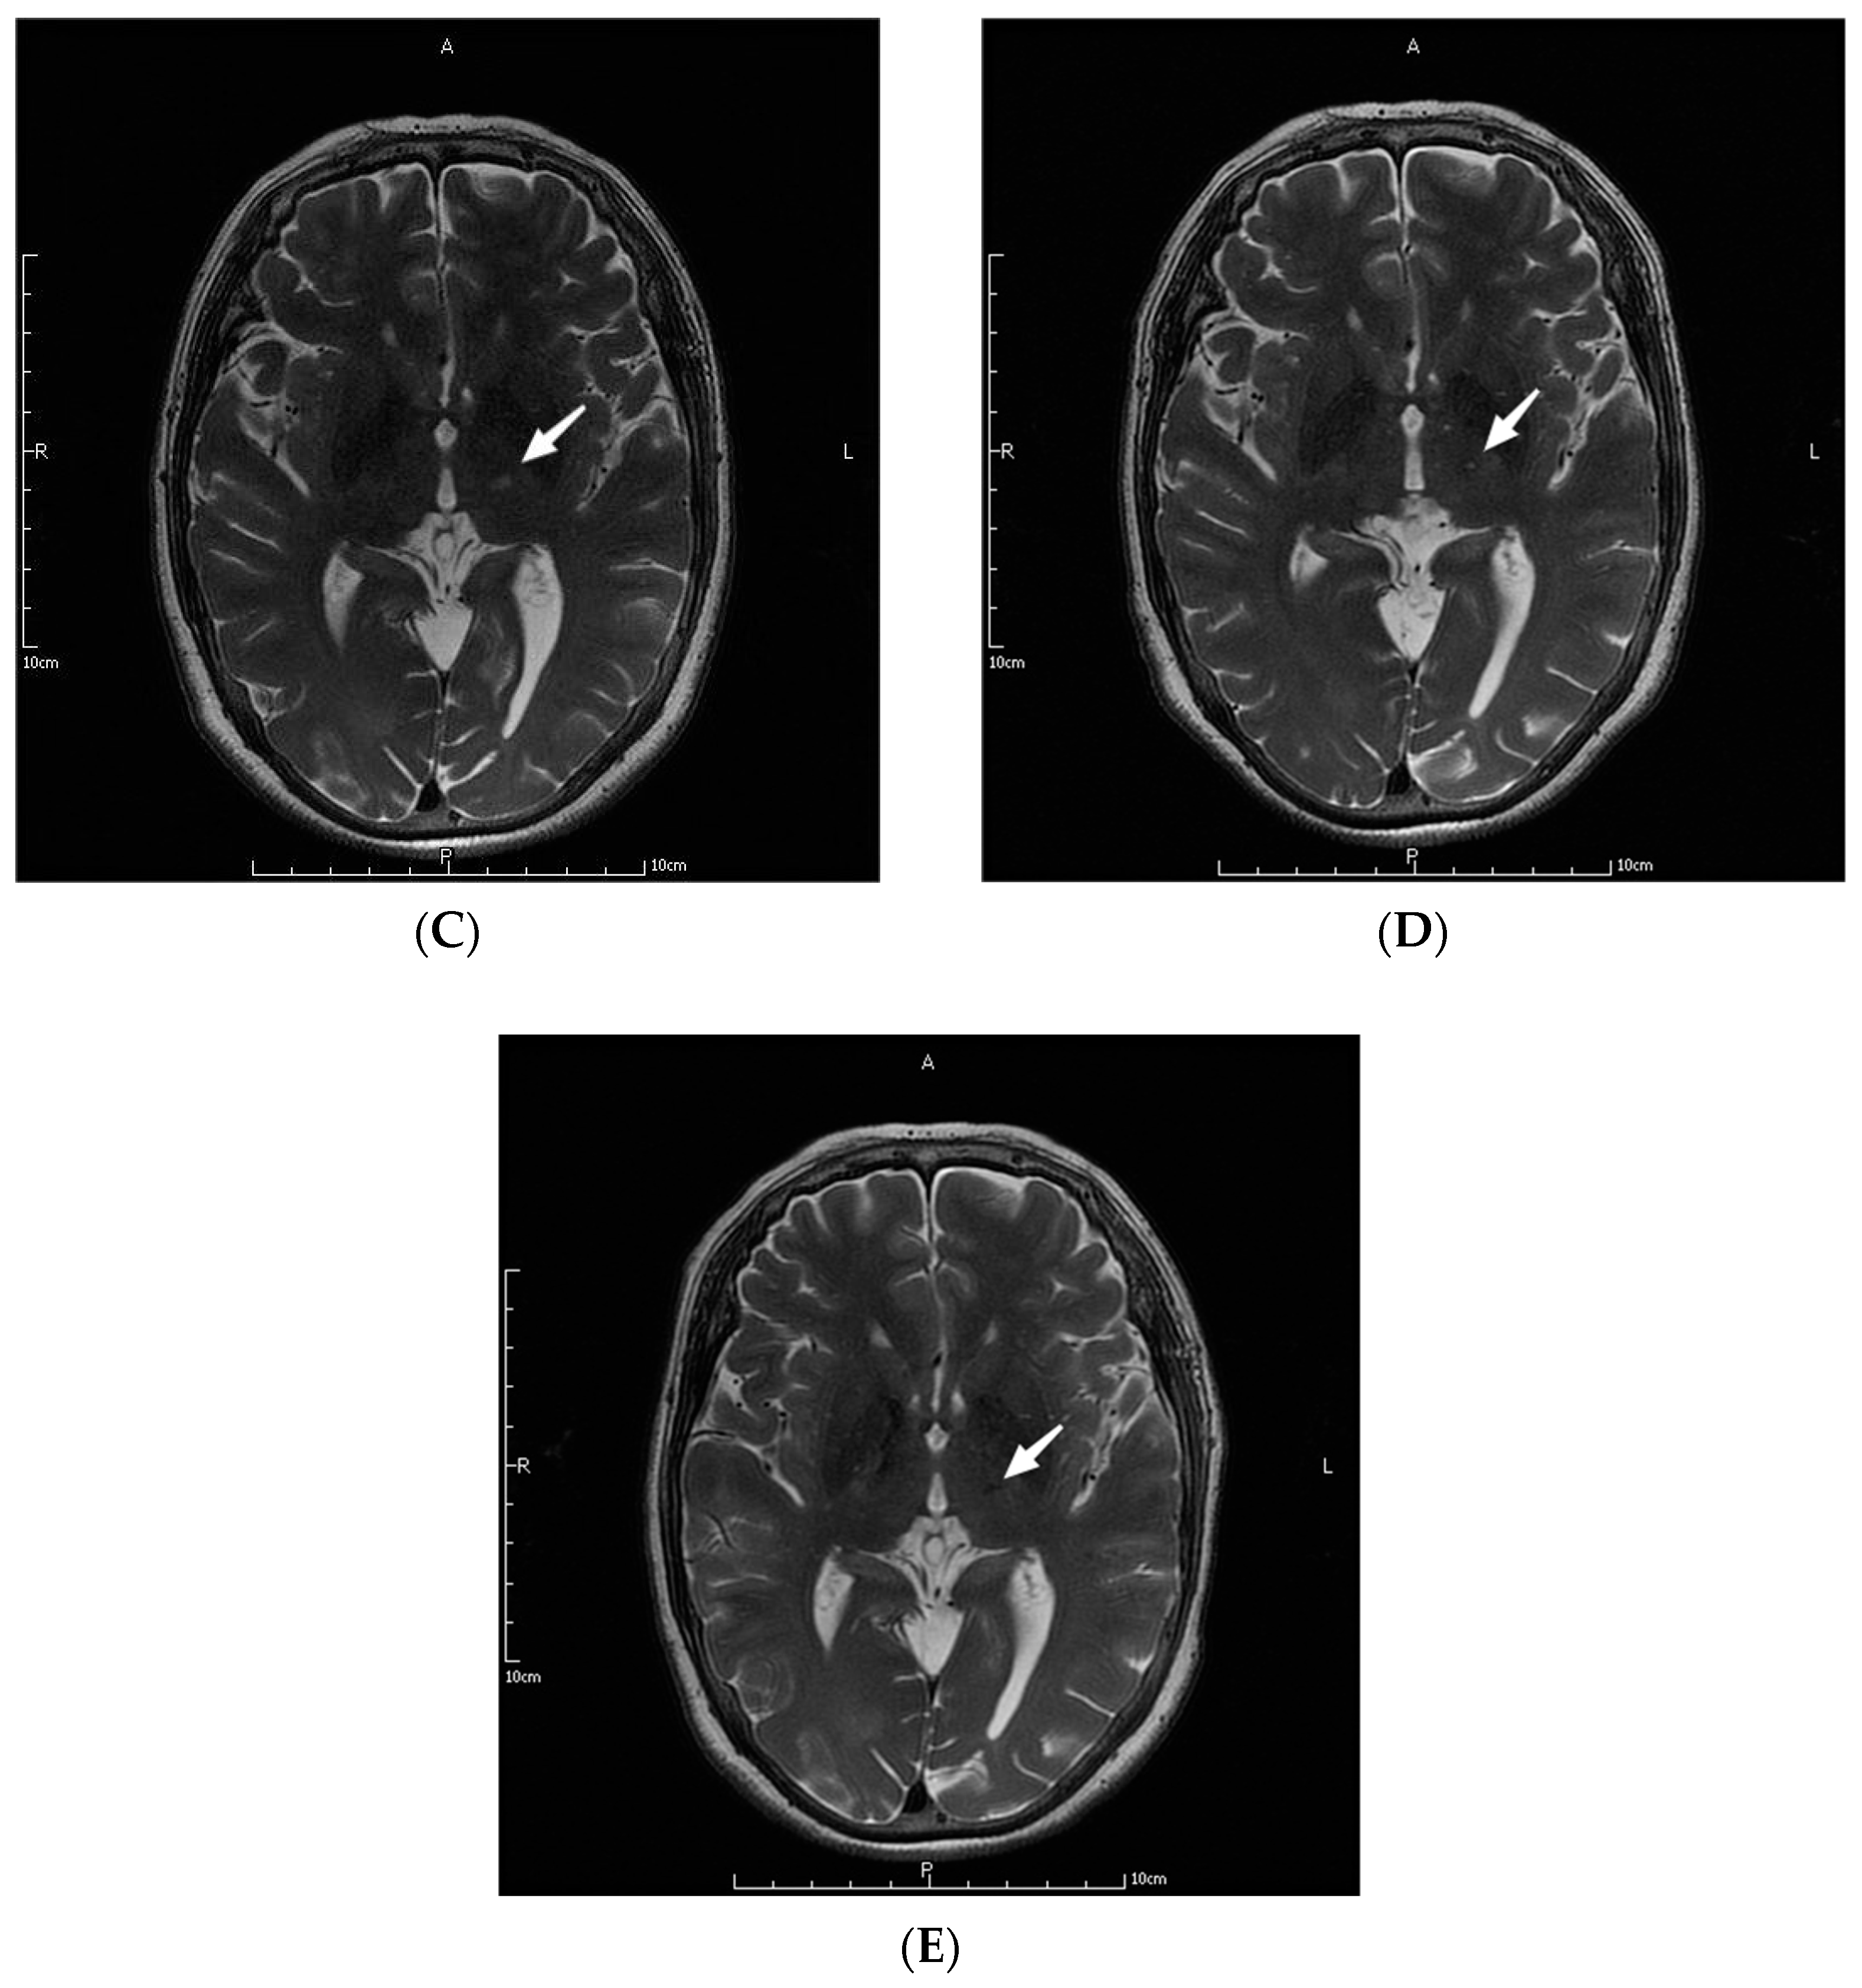

The parameters in the MRgFUS surgery were as follows: the mean ablation time of the 9 patients was 6.22 ± 2.64 s, and the average maximum temperature was 57.89 ± 1.36 °C. Figure 1 shows the MRI images of the patient No. 3 before, during, and at one month, three months, and one year after the operation.

Figure 1.

MRI images of a patient before (A), during (B), and at one month (C), three months (D), and one year (E) after the operation. The letters in the pictures are abbreviations of anterior (A), posterior (P), left (L) and right (R). The white arrow pointed to the lesions created by MRgFUS Vim ablation.